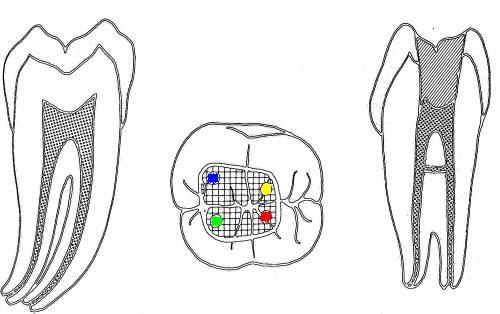

| 2º molar inferior (1,2,23,27)

Similar al primer molar inferior pero menos voluminoso, en la

raíz mesial siempre encontrará dos conductos y en la raíz distal

puede encontrar uno ó dos conductos.

-

En azul conducto mesiovetibular

En verde conducto mesiolingual

En rojo conducto distal

En amarillo un cuarto conducto,

si el conducto distal se encuentra desplazado hacia lingual,

existe una alta posibilidad de encontrar un cuarto conducto

|

| 1º Molar

inferior: El orificio de entrada del

conducto distal se encuentra ensanchado

en sentido buco lingual, debe sospechar

la existencia de un cuarto conducto.

La localización

de un cuarto conducto se lleva a cabo

con la

técnica radiológica de Clark

o por

medio de una lima curvada en distal para

sondear la pared lingual ó vestibular

del conducto distal. Imagen inferior |